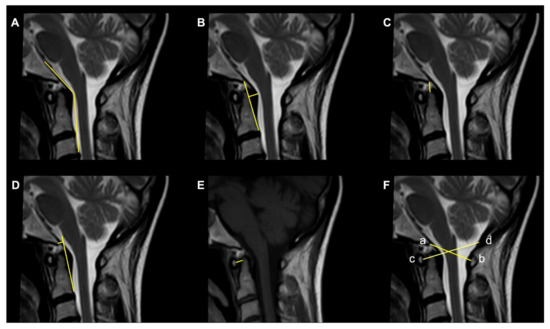

The symptoms induced by CVJ instability may range from neck pain and restricted neck movements to sensory and motor abnormalities and gait instability [68]. The concept of CVJ instability is based on both bony abnormalities and on excessive laxity/loss of insertion of the atlanto-occipital and atlantoaxial ligaments. The combination of a hypoplastic dens in association with anomalies of the posterior arch of the atlas increases the risk for craniocervical instability. Injuries to the anterior atlanto-occipital membrane, the apical and alar ligaments, the cruciate ligaments and the tectorial membrane result in instability since these ligaments provide most of the stability to the atlanto-occipital joint [69]. Thin-section multidetector dynamic CTs of the craniocervical region with sagittal and coronal sections, lateral radiographs of flexion/extension and dynamic MRIs of flexion/extension are the studies of choice to evaluate the stability of the CVJ [70]. The radiological measurements most commonly used for the diagnosis of CVJ instability include (Figure 3):

Figure 3.

Commonly used radiological parameters to predict CVJ instability. (A) Clivoaxial Angle (CXA). (B) Grabb–Oakes line. (C) Basion–Dens Interval (BDI). (D) Basion–Axial Interval (BAI). (E) Atlantodental Interval (ADI). (F) Powers ratio: ab/cd.

- The Clivoaxial Angle (CXA), which is the angle between the clivus line and the posterior axial line, examines the brainstem deformity induced by the odontoid process. A CXA of 135 degrees or less is considered “potentially pathological” [71].

- The Grabb–Oakes line, which is the perpendicular distance from the dura to the line drawn from the basion to the posterior inferior edge of the C2 vertebra. It is a measure of the encroachment of the odontoid process into the upper spinal canal (basilar invagination) and investigates ventral brainstem compression. A measurement ≥9 mm is considered pathological [68].

- The Basion–Dens Interval (BDI) measures the vertical distance between the basion and the dens and is considered pathological if ≥10 mm [72].

- The Basion–Axial Interval (BAI) is the distance from the tip of the basion to the posterior axial line and is pathological if ≥12 mm [72].

- The translational BAI and translational BDI are the change in mm of the BAI and BDI between the flexion and extension positions of the head [68].

- The Atlantodental Interval (ADI) is the distance between the posterior surface of the anterior atlas ring and the anterior surface of the odontoid process. An ADI >5 mm in adults and >4 mm in children is an indication for surgery [73].

- The Condyle–C1 interval (CC1) measures the distance between the occipital condyle and C1 at four equidistant points and is pathological in children if >4 mm, with a high diagnostic accuracy [73].

- The Powers ratio is calculated by measuring the distance between the basion and the posterior arch of the atlas and then dividing it by the distance between the opisthion and the anterior arch of the atlas [74].